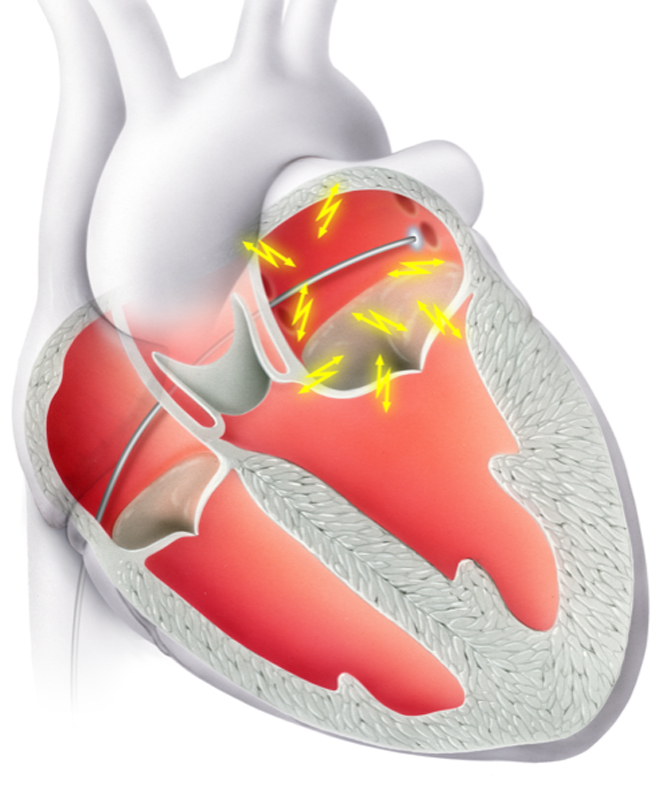

Eine bewährte Therapie bei verschiedensten Herzrhythmusstörungen, insbesondere wenn eine Rhythmuskontrolle erzielt werden soll, ist die Ablation mittels Spezialkatheter. Hierfür werden im Rahmen einer elektrophysiologischen Untersuchung (EPU) verschiedene Orte auf der Herzinnenseite, die für die Rhythmusstörungen verantwortlich sind, aufgesucht. Anschliessend wird die Elektrode des Katheters mit Hochfrequenzstrom erhitzt oder mittels Kälteabgabe angefroren. Die erzeugten Läsionen haben zum Ziel die Ausbreitung der elektrischen Impulse einzuschränken und somit die Rhythmusstörung zu eliminieren.

Eine bewährte Therapie bei verschiedensten Herzrhythmusstörungen, insbesondere wenn eine Rhythmuskontrolle erzielt werden soll, ist die Ablation mittels Spezialkatheter. Hierfür werden im Rahmen einer elektrophysiologischen Untersuchung (EPU) verschiedene Orte auf der Herzinnenseite, die für die Rhythmusstörungen verantwortlich sind, aufgesucht. Anschliessend wird die Elektrode des Katheters mit Hochfrequenzstrom erhitzt oder mittels Kälteabgabe angefroren. Die erzeugten Läsionen haben zum Ziel die Ausbreitung der elektrischen Impulse einzuschränken und somit die Rhythmusstörung zu eliminieren.

Typische Herzrhythmusstörungen, welche mittels Ablation behandelt werden können, sind:

- Vorhofflimmern (Abb 1 und 2)

Eine bewährte Therapie bei verschiedensten Herzrhythmusstörungen, insbesondere wenn eine Rhythmuskontrolle erzielt werden soll, ist die Ablation mittels Spezialkatheter. Hierfür werden im Rahmen einer elektrophysiologischen Untersuchung (EPU) verschiedene Orte auf der Herzinnenseite, die für die Rhythmusstörungen verantwortlich sind, aufgesucht. Anschliessend wird die Elektrode des Katheters mit Hochfrequenzstrom erhitzt oder mittels Kälteabgabe angefroren. Die erzeugten Läsionen haben zum Ziel die Ausbreitung der elektrischen Impulse einzuschränken und somit die Rhythmusstörung zu eliminieren.

Typische Herzrhythmusstörungen, welche mittels Ablation behandelt werden können, sind:

- Vorhofflimmern (Abb 1 und 2)